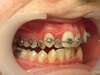

Cas n°7 traité par appareil multi-attaches - adolescent

Ce cas illustre la réussite d'un traitement orthodontico-chirurgical complexe chez un patient adolescent. La problématique initiale associait un encombrement dentaire sévère, une Classe II squelettique (mandibule en retrait) et une supraclusion marquée, verrouillant l'articulation.

Le traitement a été conduit avec des brackets autoligaturants, une technologie de pointe permettant un alignement fluide et une préparation des arcades optimale par une gestion précise des forces de friction. Cette phase orthodontique a permis de lever les compensations dentaires pour préparer l'étape chirurgicale de repositionnement mandibulaire.

Les clés du résultat :

• Harmonie faciale : L’avancée chirurgicale a radicalement équilibré le profil.

• Occlusion fonctionnelle : Obtention d'un engrènement de Classe I stable et correction totale de la supraclusion.

• Esthétique : Un sourire élargi et parfaitement aligné.

Bénéfices santé : Au-delà de l'esthétique, ce traitement protège les articulations temporo-mandibulaires (ATM) et prévient l'usure dentaire prématurée. Chez l'adolescent, cette transformation fonctionnelle et morphologique est essentielle pour la santé respiratoire, la mastication et le renforcement de l'estime de soi.